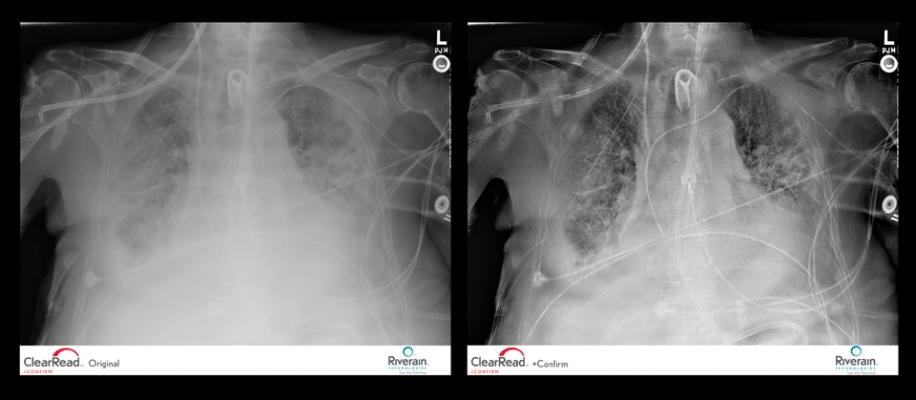

Portable chest X-ray machines are routinely used to confirm placement of lines and tubes; however, the image quality makes it challenging for radiologists to differentiate these structures, and the rib and clavicle bones obscure visibility of chest tissue by up to 40 percent. Radiologists also incur significant time adjusting the image to make the edges and tips of the devices stand out.

ClearRead +Confirm software immediately processes any portable chest X-ray, creating a second, soft tissue image with the ribs and clavicles suppressed and increasing the contrast, sharpness and visibility of tubes, lines and cardiac wires. Radiologists simply toggle between the two images to confidently and efficiently confirm proper placement of the devices.